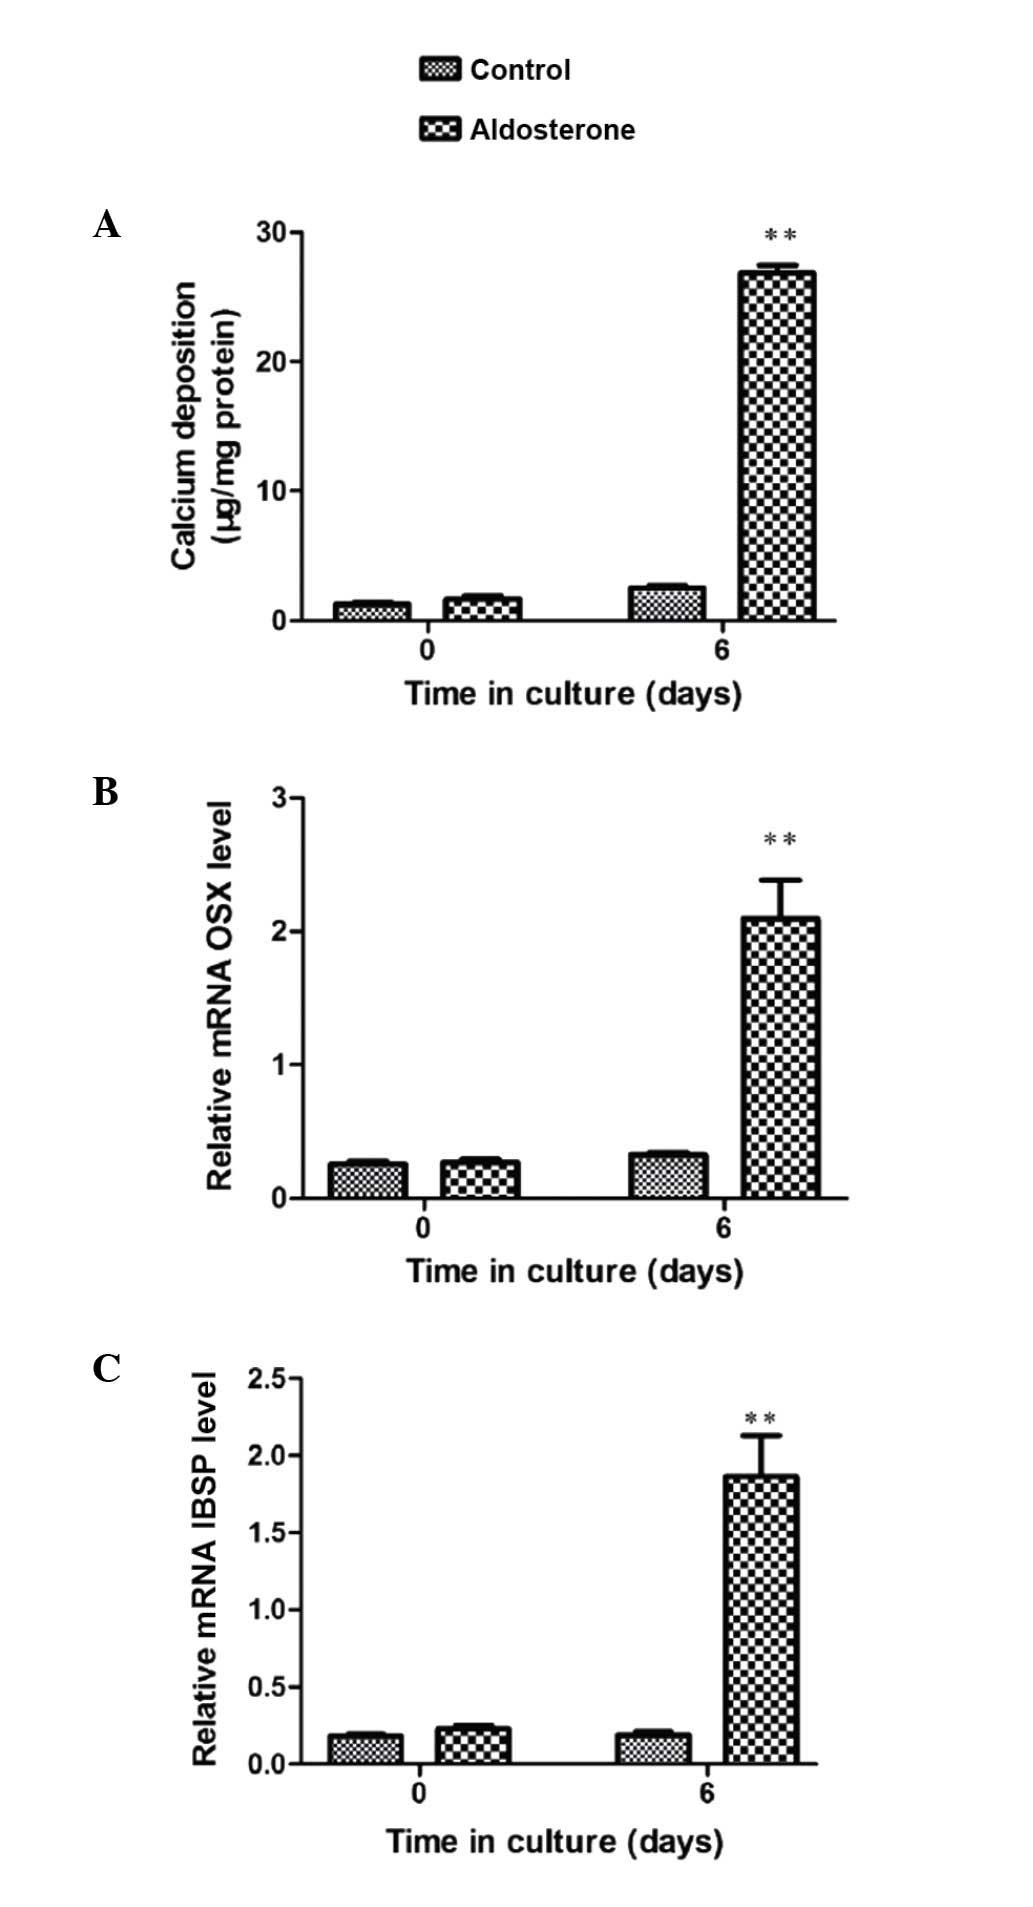

Furthermore, gene expression analysis by RT-qPCR

validated the observation of OSX enhancement. ALD-induced VSMC

calcification was significant subsequent to 6-day culture (Fig. 1A). Associated with this increase in

VSMC mineralization, OSX mRNA expression was significantly

increased at the same time point (P<0.01) (Fig. 1B). A significant increase in mRNA

expression of the osteogenic marker IBSP was observed at 6 days

(P<0.001), indicating that the transition to the osteoblast

phenotype was in progress and thereby validating this in

vitro model to study VSMC calcification (Fig. 1C).